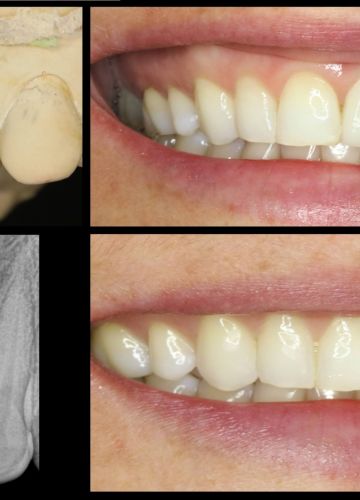

• Pēc 5 mēnešiem tika izgatavots slāņots cirkonijkeramikas kronis

• Tika  nomainītas vecās plombas priekšzobu rajonā